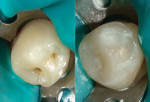

Kisby points to a recent case example of his involving an anxious, kinetic, dental- and needle-phobic 9-year-old boy who presented with possible caries on his mandibular bicuspid. An enamelplasty revealed that the stain was limited to the superficial layer of enamel. "The tooth was then rinsed and dried to slightly moist. Beautifil Kids SA was used because of its unique property of being a self-etch restorative, thus eliminating the need for etching, rinsing steps, and bonding agent, which decreased patient chairtime," he says. "Beautifil Kids SA was applied, allowed to self-etch and bond for 20 seconds, and then light-cured for 5 seconds."

Overall, Kisby says Beautifil Kids SA provides a winning combination for safe, fast, and effective pediatric restorations with a bevy of added benefits. "The unique chemistry of Beautifil Kids SA is BPA-free and provides a chemical bond as well as resin tag infiltration. The unique filler structure combines the light transmission and diffusion properties of both dentin and enamel to blend with the surrounding dentition," he says. Overall, "I have found Beautifil Kids SA to be a beneficial and easy-to-use restorative material for pediatric dentistry."